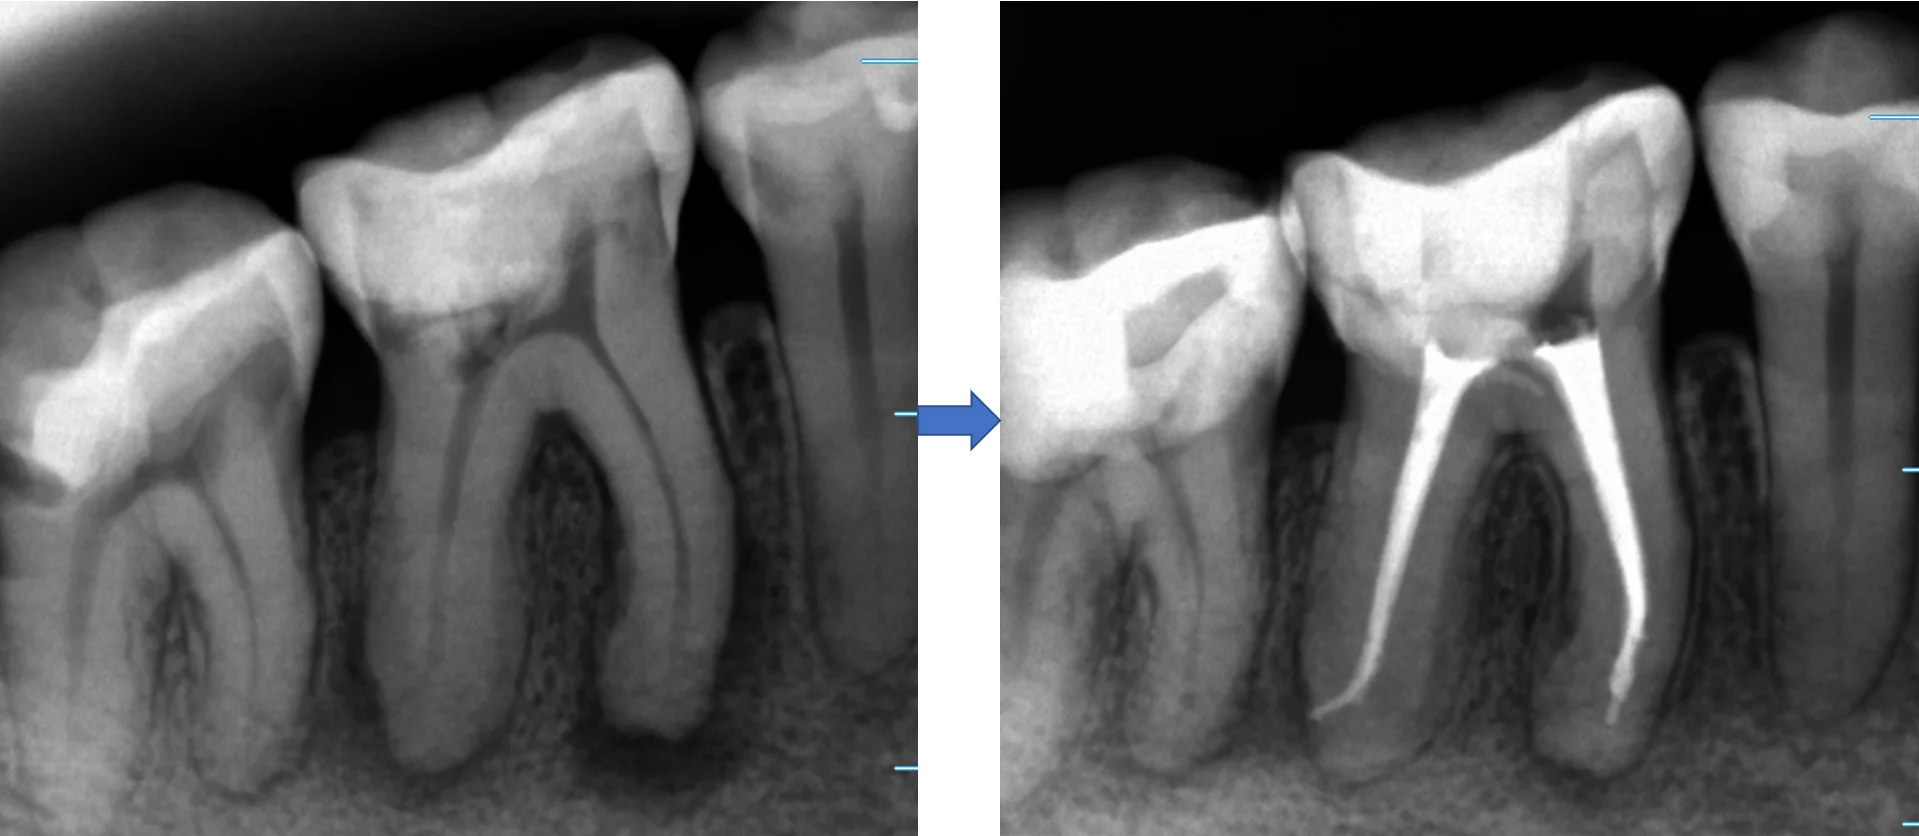

そして治療終了後の画像です

やはり根の先で大きく曲がっていました。

ちなみに、術前術後の変化がこちらです。

並べると、根の先の黒い部分が大分小さくなって、骨が出来てきているのが分かりやすいかと思います。

通常、3~4回程度で治療が完了するのですが、骨が出来るまでは半年から数年は掛かりますので、ここまで劇的に改善しているのが分かりやすいケースは少ないです。

今回は患者さんが比較的若く、骨代謝が活発な方だったので、短い治療期間でしっかりと良くなっているのが見えました。

通常は根管充填後半年から1年経ってから、もう一度レントゲンを撮らないと本当に治療が成功したかどうかは分かりませんので、今回のような場合は確実に上手くいっているのが分かるのでほっとしますね・・・(;^ω^)